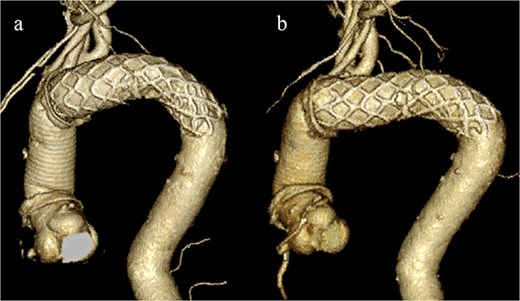

CT revealed no endoleak, but the aneurysm had enlarged to a diameter of 56 mm (Fig. 1b). Three-dimensional CT revealed straightening and proximal migration of the FET (Fig. 2). No clear signs of pulmonary parenchymal hemorrhage or findings suggestive of the mass were reported. Laboratory tests indicated mild anemia, with a hemoglobin of 9.7 g/dL and hematocrit of 29.0%. No infectious or inflammatory diseases that could cause hemoptysis were identified.

(a) Three-dimensional CT image 1 year after total arch replacement with a FET. (b) Three-dimensional CT image 2 years after total arch replacement with a FET demonstrating straightening and migration of the FET.